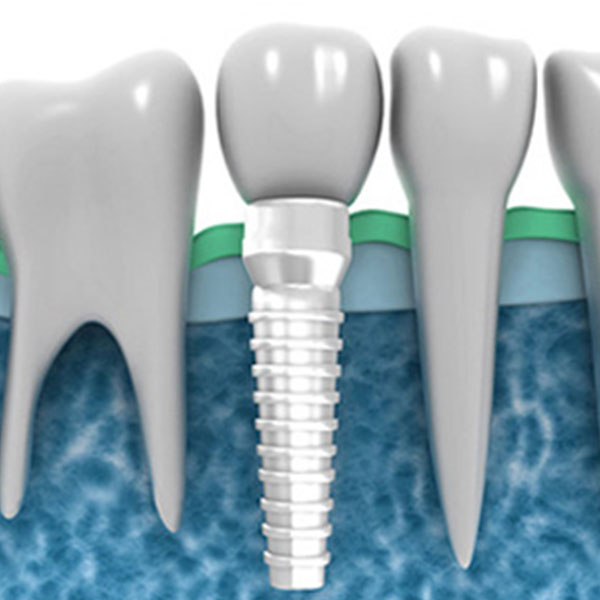

(Nobel Biocare, Schtraumann) Nedostatak jednog zuba, Totalna bezubost, Proteza na implantima, Nadogradnja kod nedostatka kosti, Podizanje poda sinusa, Lateralizacija nerva.